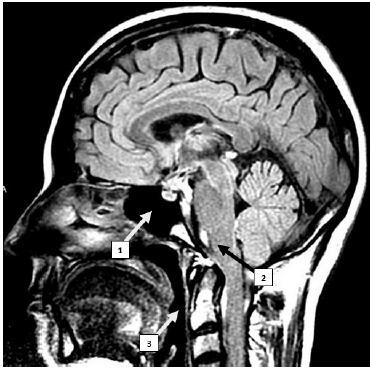

Internet: <cdiumuarama com br/exame/> Figura 3

Tendo como referência a imagem precedente, julgue o item que se segue.

A estrutura indicada pelo número 3, denominada faringe, é um órgão tubular com início logo após as coanas e possui, na sua terminação, comunicação com a laringe e o esôfago.

A primeira vértebra da região cervical, chamada de Atlas, possui articulação com os processos condilares do osso temporal, em suas facetas articulares superiores, e articulação com o áxis, em suas facetas articulares inferiores.

O número 2 indica o bulbo, um centro de comando respiratório autônomo, em cuja região caudal ocorre o cruzamento de fibras nervosas, que constitui a decussação das pirâmides.

A estrutura indicada pelo número 1 corresponde ao seio etmoidal, uma cavidade oca revestida com mucosa e preenchida com ar.

A imagem apresenta um corte coronal mediano, que divide o corpo em direito e esquerdo.